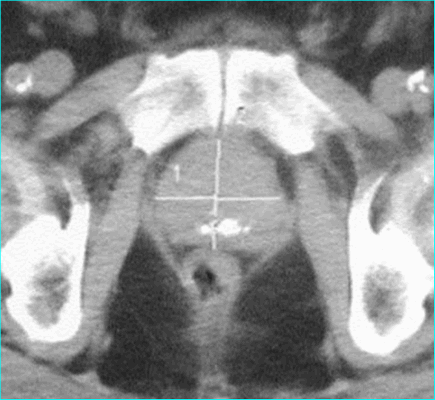

Область интереса на томограмме малого таза

Рак ПЖ T4 (КТ)